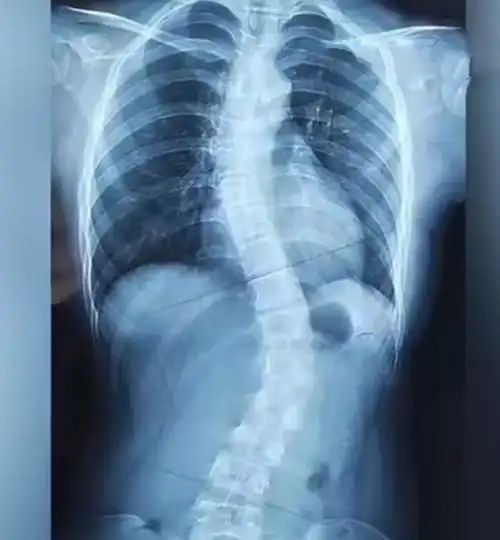

弯腰的时候脊柱凸出

康睿仕案例分享: 13岁脊柱侧弯15度,康复训练15次矫正10度恢复

12岁脊柱侧弯48度(线下一次)

冲上热搜13岁女孩脊柱严重侧弯她的坏习惯很多云南人都有